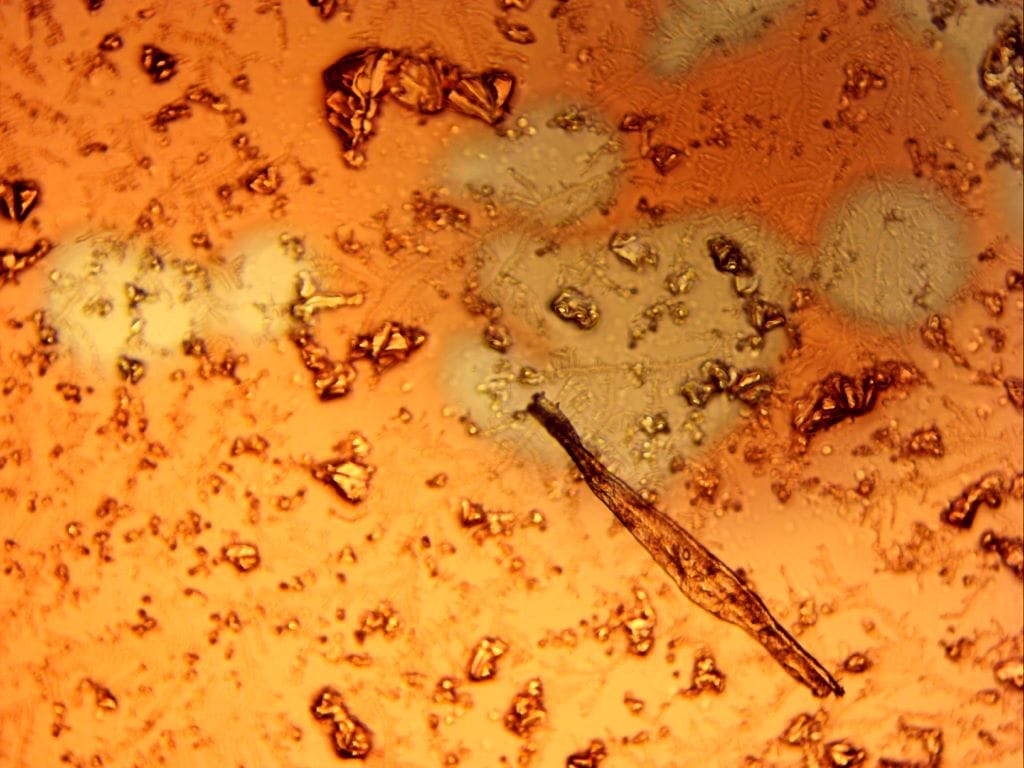

Startling Pictures Paint Many Words

Here are the first few microscope images we took that showed us, starting within minutes of beginning to look, in January 2022, that the Pfizer vax appeared ‘spiked’. All we should see based on the ingredients is a bland emulsion, looking a bit like milk, or cloudy beer. The MOH says these pictures are faked, but our sworn statement to NZ police in complaint 220217/0669 says they aren’t, and we were careful with our technique. The slides and coverslips were clean and high quality. The pictures are between 100x and 1200x magnification with an ordinary light microscope – so they look shocking at this enlargement, and are shocking, since they should not show much at all. Remember though, there are two secret ingredients, largely thought to be a military-grade “hydrogel”: a witch’s brew of who knows what.

These structures below became visible from the gloomy emulsion background after about 30 minutes. Note the background of small ‘doughnut rings’, but far too large to be Pfizer’s lipid nanoparticles, supposedly the only ‘structure’ in the vials. The small spheres are about 3 microns in diameter. 1000 microns = 1 mm. Dismissing them as “just crystals” is over simplistic. Of what? Why? Where else are they found like this?

These next two are both of the same 3-D structure, with other shapes associated with it, and the third shows unknown structures. There are many other slides we will upload later.

Finally, although we have hundreds of pictures, here is a favourite, several hours after a drop of ‘vaccine’ was mixed with blood. Explanations on a postcard, please….